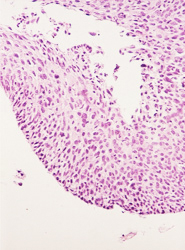

El resultado de una valoración colposcópica de paciente con lesión displásica siempre será confirmado por el estudio histopatológico que realiza el médico anatomopatólogo (estudio de la biopsia tomada en la colposcopía) . A continuación presentamos imágenes histológicas con sus diagnósticos.

• Lesion de alto grado, con anisocitosis y anisocariosis severas, perdida de la cohesividad y orientacion celular.